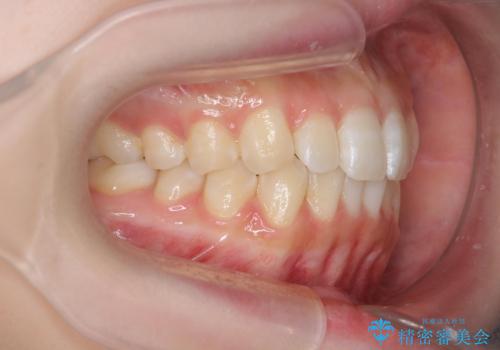

前歯のねじれを治したい マウスピース矯正治療

- 前歯のねじれを改善し、きれいな歯並びにしたい!と矯正治療を希望され来院されました。

マウスピース矯正システム、インビザラインのシミュレーションを用いて最終的な歯の位置をしっかりと確認したのち、きれいな歯並びとなるようマウスピース矯正治療を開始します。

ねじれとともに突き出たように見えていた前歯も見た目が大きく改善し、喜んでいただくことができました。